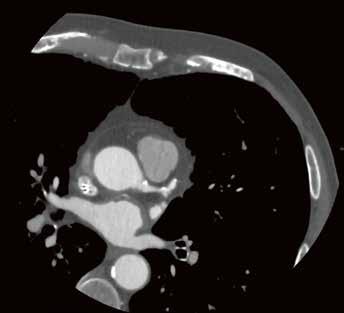

65-jähriger männlicher Patient; Abb. links: Notaufnahme Röntgen Liegendthorax bei Verdacht auf COVID-19-Pneumonie, Abb. rechts: CT-Bestätigung der COVID-19-Pneumonie am gleichen Tag.